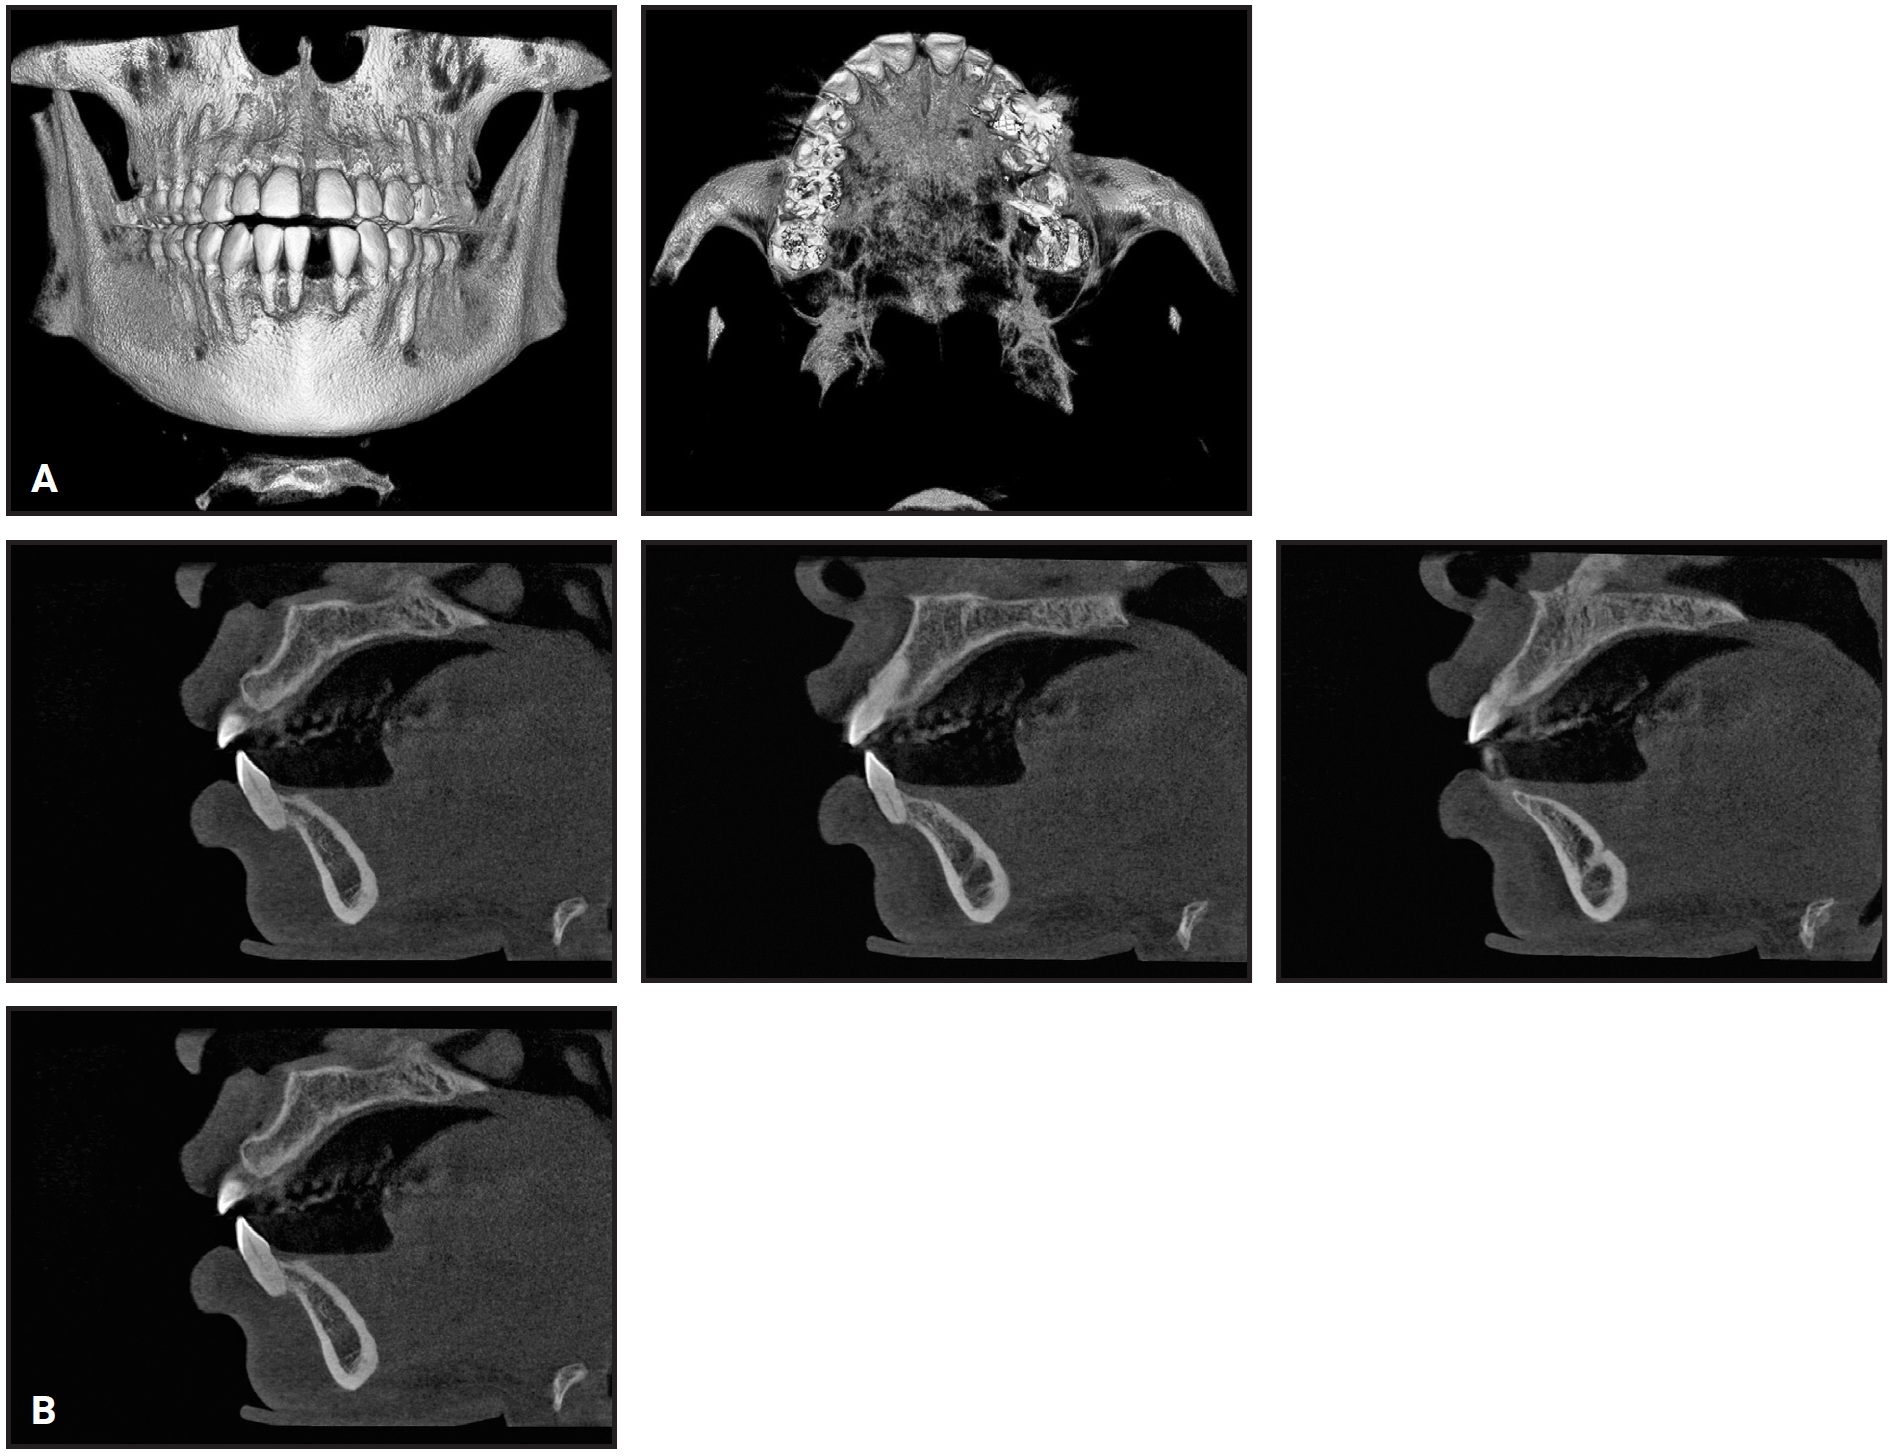

This example shows a 27-year-old female patient with a compensated Class II malocclusion (see attached video in the online version of this article). Note that the lower incisors are excessively proclined (IMPA of about 110°) in the pretreatment lateral cephalogram (Fig. 1).

Presenting to our office 18 months after completing a previous treatment, the patient had lost her lower left central incisor (Fig. 2). In an effort to reduce the lower-incisor proclination, the teeth were torqued at levels that might have appeared to be customary but were incompatible with the alveolar-housing anatomy.

Before torquing, we as orthodontic specialists need to understand the alveolar-housing anatomy to prevent dehiscence and fenestrations.

Fig. 1 Patient with compensated Class II malocclusion (Class I dental, Class II skeletal) before treatment. Lateral cephalogram indicates proclined lower incisors, with IMPA of about 110°.

Fig. 2 A. Three-dimensional volumetric reconstruction of cone-beam computed tomography (CBCT) taken 18 months after patient completed treatment with previous orthodontist, showing loss of lower left central incisor and dehiscence of remaining lower-incisor roots from alveolar housing. B. Sagittal CBCT slices of upper right canine, first premolar (missing), second premolar, and first molar, confirming root positions incompatible with alveolar-housing anatomy.